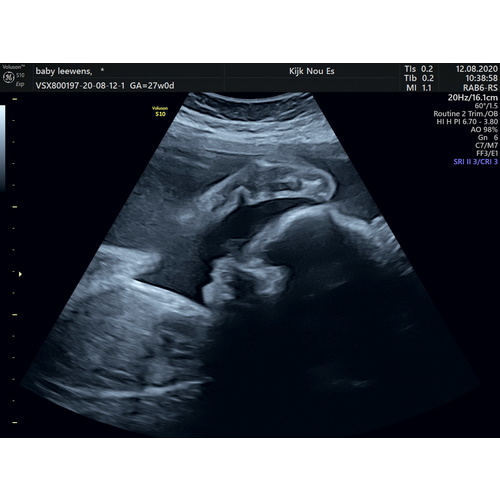

Niet perse grappig, misschien eerder een beetje eng. Maar een paar keer moe ...

Haha, ik moest even goed kijken. Lijkt inderdaad wel op een gezicht!